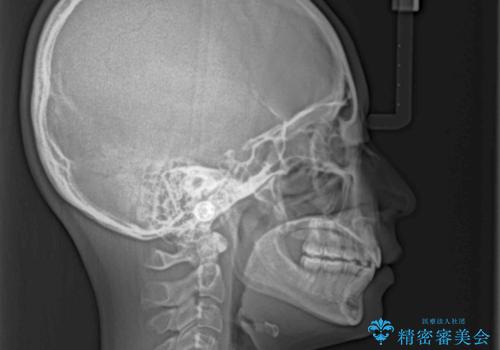

- 上下の前歯が突出しており、口が閉じにくいとのことで来院された患者様です。

上下前歯が著しく前突している状態であったので、上下左右の第1小臼歯4本を抜歯し、ワイヤー装置にて矯正治療を行うこととしました。

舌の突出癖により、前突になったと考えられたため、舌のトレーニングをしっかりと行うよう指導しました。

舌の突出癖があり、前歯の移動量も多くなるため、治療期間は長くなると予想されましたが、13ヶ月という予定の半分程度の期間で終えることができました。